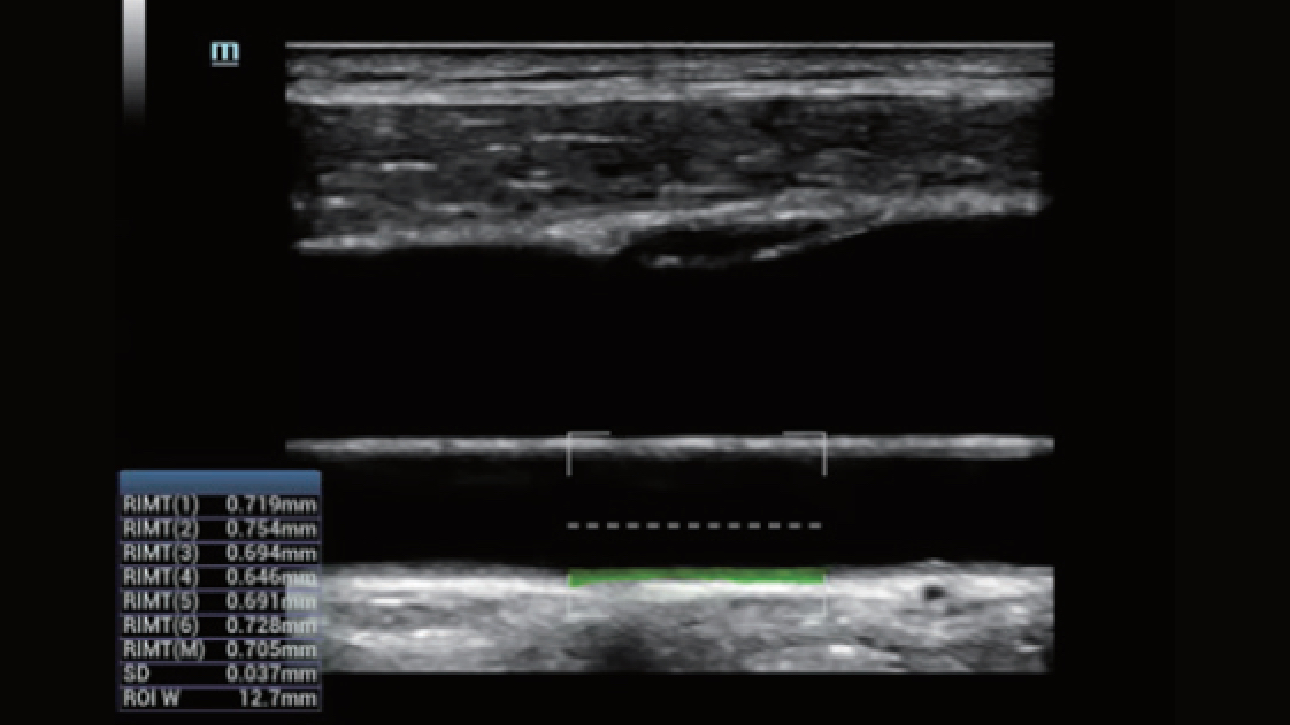

Clinical Images